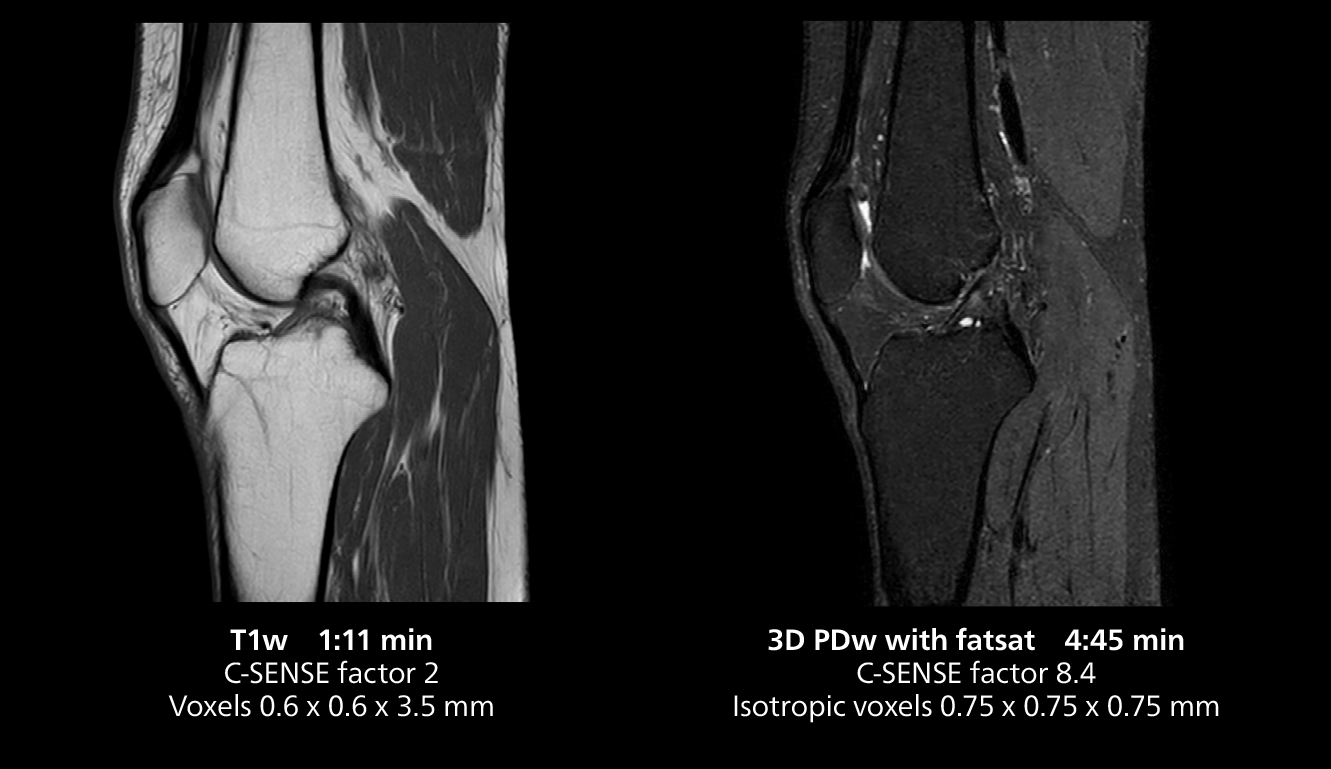

3D knee imaging

The isotropic high resolution 3D sequence in this MRI case allows for reformatting to obtain other orientations with high quality. Acquired on the MR 5300 system.

The MR 5300 with Compressed SENSE is up to 50%** faster for many exams. It can provide routine exams in less than 5 minutes and whole-body exams in less than 20 minutes. Saint-Augustin has taken advantage of that speed to create highly efficient protocols. The hospital’s standard stroke protocol is just about 8 minutes, and standard ENT, prostate PIRADS staging, and endometriosis studies all clock in at just about 10 minutes.***

“We have more speed in 3D sequences,” Dr. Gellée states. “With Compressed SENSE, we can replace two or three 2D scans withone high-quality 3D scan. High quality additional orientations are then obtained by post-processing of the 3D data set, thus saving scanning time.”